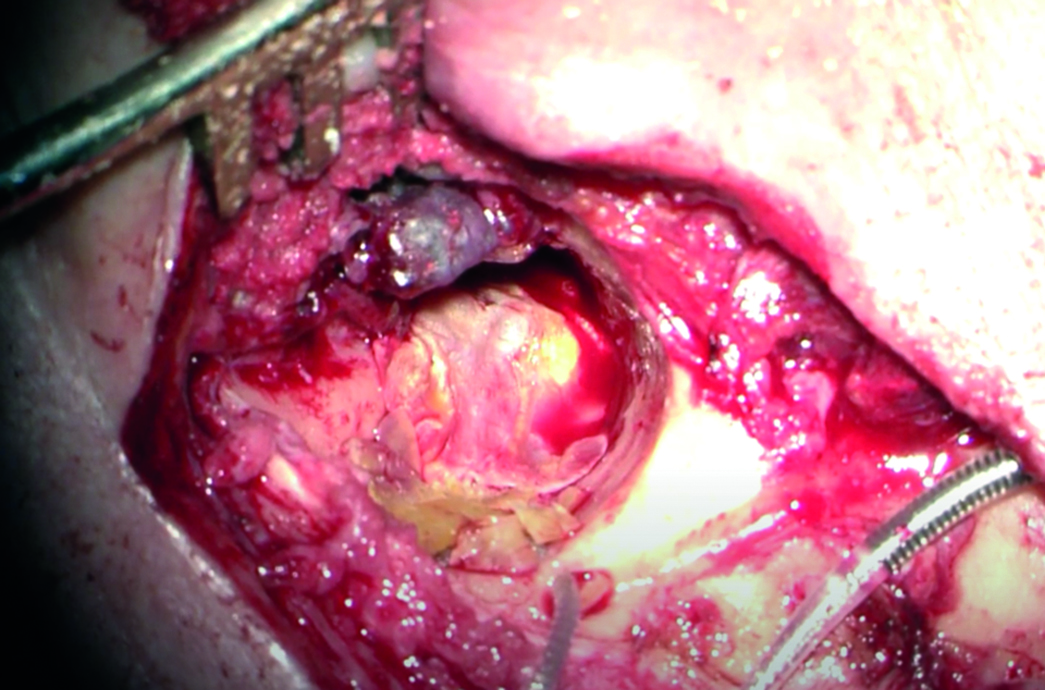

У пациентов с ранее проведенной радикальной операцией на имплантированном ухе рецидива холестеатомы не выявлено. Сложность проведения КИ заключалась в укладке и фиксации активного электрода в мастоидальном и барабанном сегментах для предотвращения его экструзии. Для этого электрод укрывали аутохрящом и аутофасцией. У пяти пациентов использовался аллохрящ (рисунок 4). За весь период наблюдения экструзии электрода не отмечено.

Рисунок 4. Интраоперационное фото укрытия электрода аутофасцией и аллогенным хрящом при проведении кохлеарной имплантации после радикальной операции на левом ухе.

Figure 4. Intraoperative photo of the electrode being covered with autofasciation and allogeneic cartilage during cochlear implantation after radical surgery of the left ear.